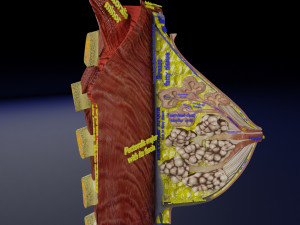

This is a 1:1 scaled model of right breast cut opened in sagittal plane to reveal its internal antomy and histology (schematic). The deeper parts and fascial layers are also depicted to give a very detailed approach to the model. The full layers starting from skin, nipple areola, till intercodtal muscles and ribs are also depicted.